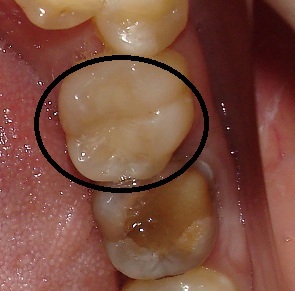

Пример 2.

Эта пломба простояла 4 года.

Видно отслоение материала и кариозный процесс под ним (тёмная полоска между зубами).